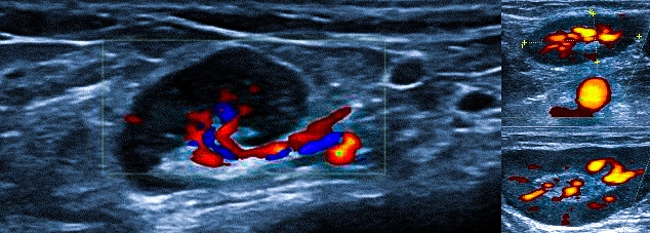

УЗИ с допплерографией у онкологических пациентов обнаруживает следующие изменения в структуре лимфоузлов:

- увеличение размеров — обычно до 6-6,5 см;

- шарообразную деформацию или неправильные контуры;

- спаянность в виде конгломератов;

- отсутствие отчетливой дифференциации на кору и ворота;

- неоднородную структуру, включая области с измененной эхогенностью;

- жидкостные включения и кальцинаты;

- усиление кровотока и образование новых сосудов (ангиогенез).

Такого рода изменения чаще всего выявляются при лимфоме.